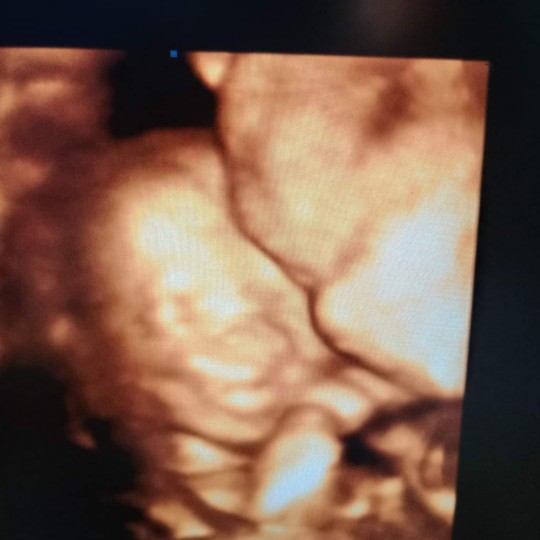

มีคนมาว่าแม่นับวันผิดบ้างหละ คลอดก่อนกำหนดบ้างหละ คือรูปนี้นานแล้ว ตอน16wแล้ว แม่ลงนานแล้วนะค้ะ ตอนนี้ก็ 28wละจ้าา บ้านนี้กำหนดคลอด28มิ.ย.63 เพศชายจ้า?